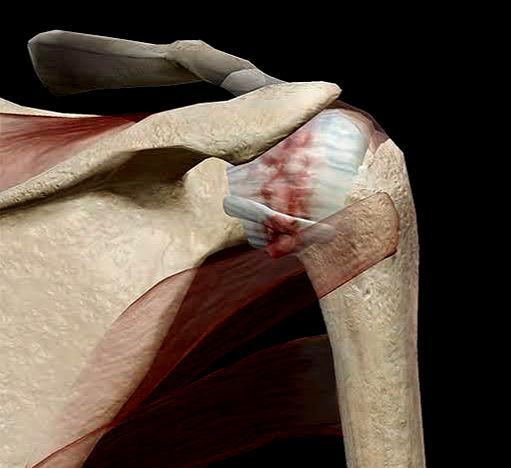

先和大家说一下,看到这篇文章的时候呢,千万不要担心,大部分的肩关节疼痛都是由于肩关节本身的问题,比如肩关节的炎症、肩关节骨头的增生肩关节内肩袖的撕裂等导致的,另外还有一部分是由于颈椎神经的压迫导致的,因为癌症导致肩痛的病例是非常少的。

比如肩关节撞击综合症的患者在甩动肩膀的时候,尤其在做上举肩膀的时候会诱发疼痛,疼痛可能会持续1~2天,但休息会缓解。

图片

癌症诱发的肩痛往往与活动并不相关,或者是相关性不大。比如肩关节撞击综合症,或者是肩袖撕裂患者会在某一个固定动作的时候诱发明显的疼痛,比如肩周炎的患者,由于肩关节出现了明显的粘连,在做旋转动作的时候会诱发明显的疼痛,比如梳头、比如提裤子的时候,会诱发明显的疼痛。